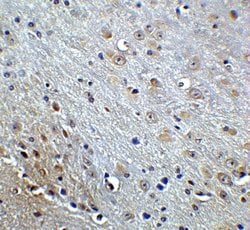

Invitrogen™ Amyloid Precursor Protein Polyclonal Antibody

Brand: Invitrogen™ PA520737

A suggested positive control is rat brain tissue lysate. PA5-20737 can be used with blocking peptide PEP-0851.

Amyloid Precursor Protein (APP) or Amyloid beta precursor protein functions as a cell surface kinesin I membrane receptor, mediating the axonal transport of beta-secretase and presenilin 1. APP is important for neurite growth, neuronal adhesion and axonogenesis. APP is a 100-140 kDa transmembrane glycoprotein that exists as several isoforms resulting from alternative splicing. Proteolytic cleavage of APP by beta- and gamma-secretases results in the generation of beta amyloid, which is the primary component of senile plaques. Senile plaques are one of the major histopathologic features of Alzheimer's disease. Abnormal regulation and processing of APP also plays a role in Down's syndrome, early onset familial Alzheimer's disease, and cerebral hemorrhage.

| Immunohistochemistry, Western Blot | |

| The immunogen is a 18 amino acid synthetic peptide within amino acids 180 - 230 of human Amyloid Precursor Protein (APP). | |

| Human, Mouse, Rat | |